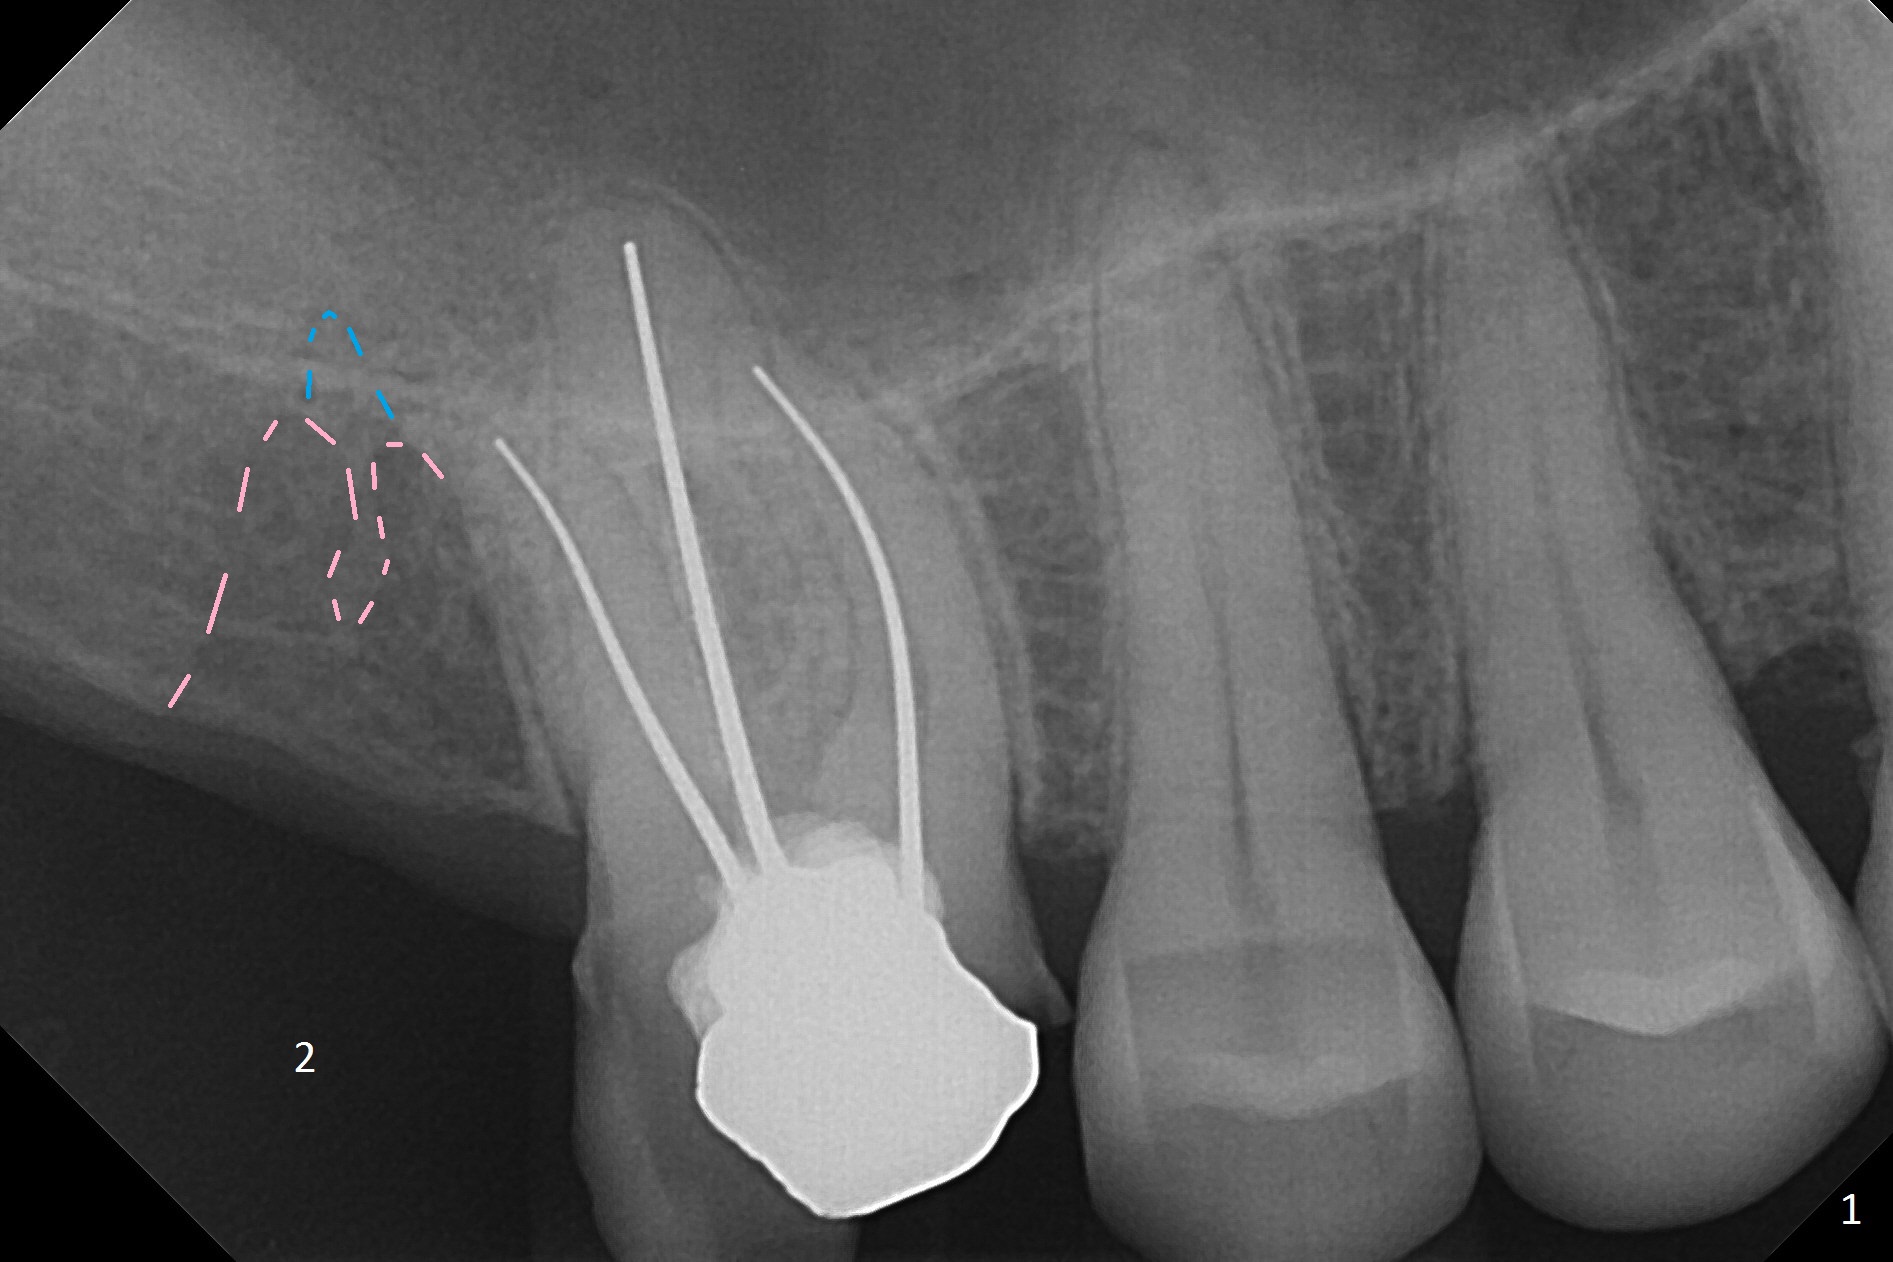

A 59-year-old man had #2 extracted approximately 4 months earlier (Fig.1 pink: possible buccal sockets; blue: palatal one). The edentulous ridge seems to be wide with exostosis (Fig.2 yellow line). Use Magic Split for access and initial bone expansion, followed by Magic expanders. The initial depth will be 7 mm to avoid sinus membrane perforation. Place PRF membranes and bone graft prior to inserting a 4 mm dummy implant. Periodontal dressing may be applied to the rugged surface of the tooth #3 for increased retention. Or a splinted provisional will be fabricated.